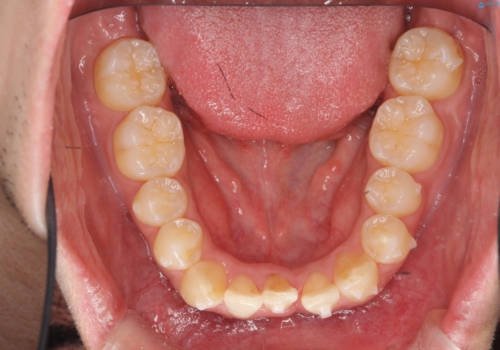

下の前歯が3本になり奇数になることで、上下の真ん中は一致しませんが、そこまで目立たないと思います。

残りは全て天然歯になり、人工物の心配をしなくて済むようになりました。

治療も順調に進み、リファインメントも1回のみで済んでいます。

ブラックトライアングルも少なめで、短期間でしっかり並びました。

下の前歯の歯槽骨が一番薄く、歯肉退縮のリスクがあるため、今回のような1本抜歯も選択肢の一つです。